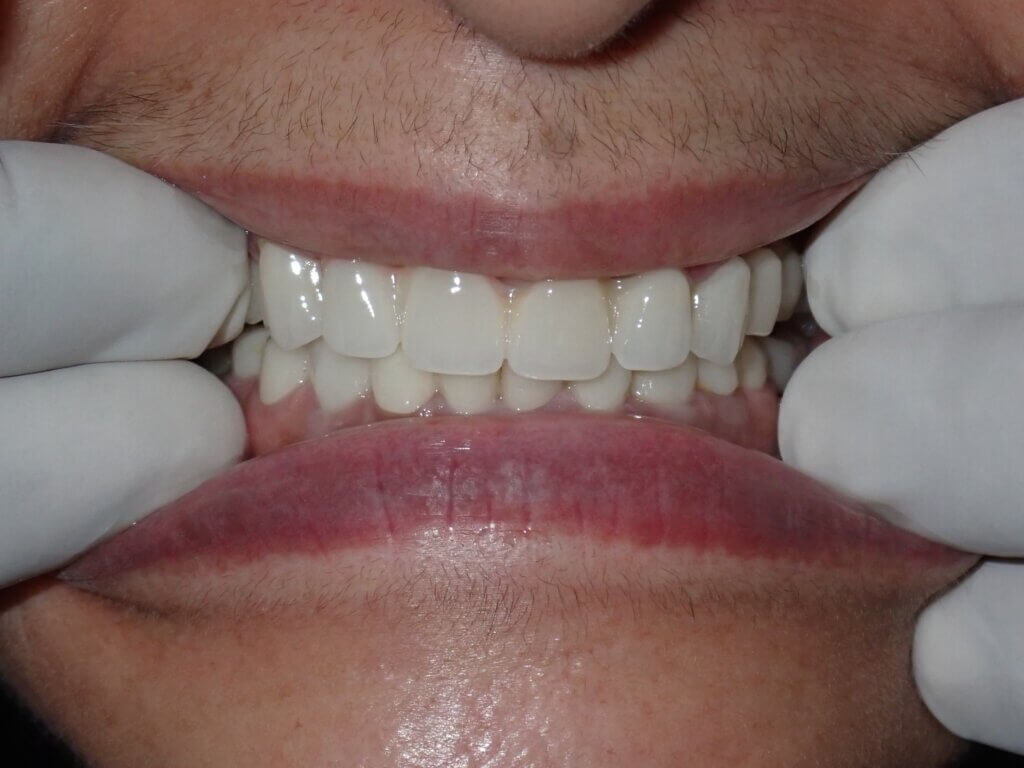

ushma Sethi India Post Treatment1 20240907

After

The patient adapted very well to the new crowns and bridge, reporting immediate improvement in chewing efficiency. Over time, she regained confidence in her smile and was able to enjoy a wider variety of foods without discomfort.

Healing was smooth, and follow-ups confirmed excellent oral health stability and patient satisfaction.